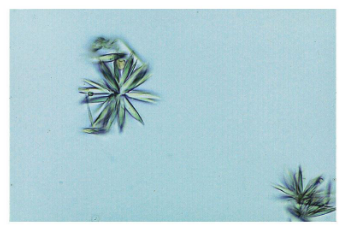

Most clinically significant crystals in urine?

Cystine, Leucine, and Tyrocine

Calcium oxalate- Acid/alkaline

Envelopes or dumbells

most common form of kidney stone, ingestion of Ethylene glycol, vegetarian diet.

Monosodium Urate- Acidic

thin needles, pencil like small clusters

Gout

Uric acid- Acidic

Rhombic plates,

Can be seen after chemotherapy or gout

Cystine- Acidic/Alkaline

Clinically significant, hereditary cystinosis or cystinuria, renal damage, confirmatory test needed.

Cholesterol- Acidic

Tyrosine- Acidic

Leucine- Acidic